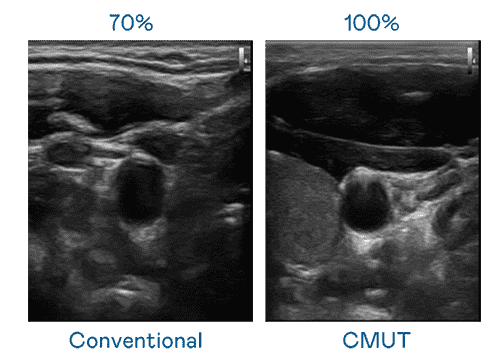

CMUT 技术是一种用电容式微机电元件来产生超音波讯号的技术。。与传统 PZT 压电式技术相比,,,,CMUT 频宽增加 30%,,,,更宽频的超音波讯号让影像解析度大幅提升,,,,是实现高影像品质医疗超音波扫描、、、促进精准医疗发展的关键技术。。

大频宽带来超清晰影像

超音波影像的解析度高低,,,首先取决于探头能发出的讯号频宽。。。至成国际 CMUT 可提供高清晰的超音波讯号,,,提供高频宽、、高灵敏度、、影像纹理细节更高的超音波影像,,,协助医护人员缩短影像判读时间及利用精准的医疗影像进行诊断。。。。